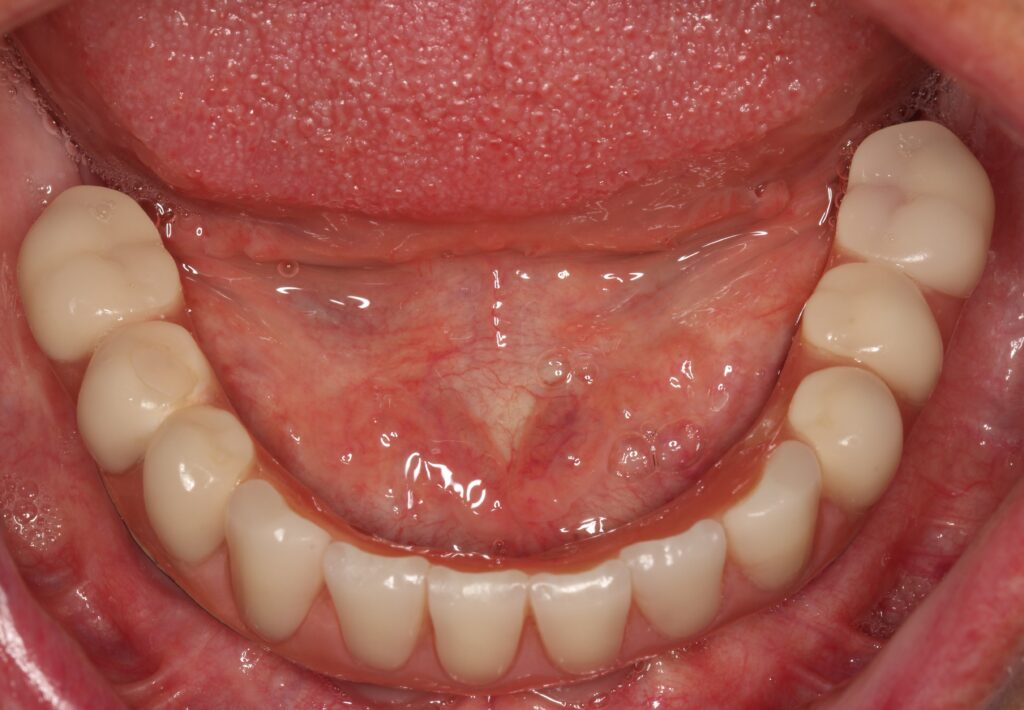

A selection of full arch fixed implant bridge patients after 5 years of wear